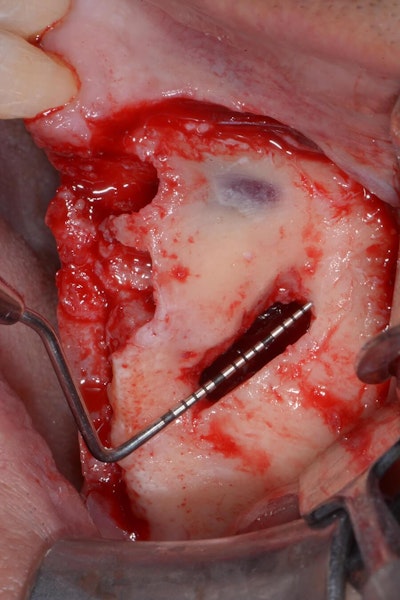

An incision is made along the crest with vertical releasing incisions to obtain access to the lateral and anterior walls of the sinus. The extension of the flap is smaller than a traditional sinus elevation. Once a full-thickness flap is elevated, a small antrostomy is made parallel to the anterior sinus wall starting 3 mm distal to it and then extending anteriorly to reach the anterior sinus wall. The antrostomy is usually 4 to 6 mm mesiodistally and 7 to 8 mm apicocoronally. This simplified antrostomy design is preferred because extension of the antrostomy to the anterior wall renders the membrane elevation procedure simpler and safer by providing direct visual access to the narrow anterior portion of the sinus. This results in a reduced membrane perforation rate (Fig 2a-b).

The antrostomy is parallel to the anterior sinus wall. The membrane has been distally displaced and the nasal mucosa is gently elevated to allow implant site preparation.

Distal displacement of the sinus membrane allows for the placement of an implant with a distal tilt of 30 degrees (Fig. 3). The direction of the first implant drill can be observed through the antrostomy. The preparation of the implant site extends apically through the anterior sinus wall into the cortical layer of the often adjoining lateral nasal wall. After verification of the implant axis using direction indicators, the drilling sequence is finalized and a bone substitute is inserted (on average, 1 mL of graft material is needed). The implant is then inserted through the residual crestal bone into the grafted sinus where the membrane has been previously displaced distally. It engages apically at the M point, the confluence of three cortical walls. In some cases, it may be possible to obtain satisfactory implant stability without engaging the lateral nasal wall cortex. This approach further simplifies the surgical procedure.

The implant drill is used at a 30 degree angle.